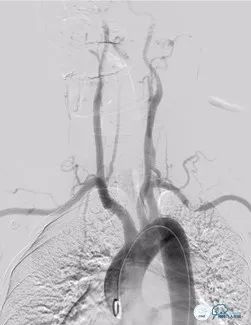

入院急查全脑血管造影术:可见基底动脉高密度征。

图2